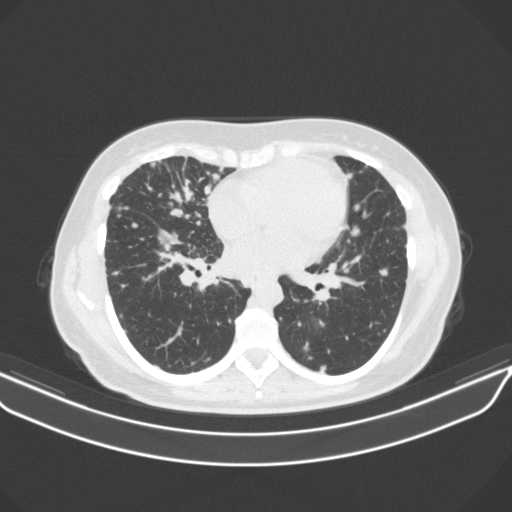

Targeted Slice 70 - Lung Window Analysis (Generated vs Real Venous)

0.752

Lung SSIM

110.9

Lung RMSE

46.5

Lung MAE

Average Lung Window Metrics Across All Slices (133 slices) - Generated vs Real Venous

0.749

Lung SSIM (Avg)

109.7

Lung RMSE (Avg)

44.6

Lung MAE (Avg)

Original NATIVE CT scan (input)

Lung window (WL -600, WW 1500 β†’ Low βˆ’1350, High +150)